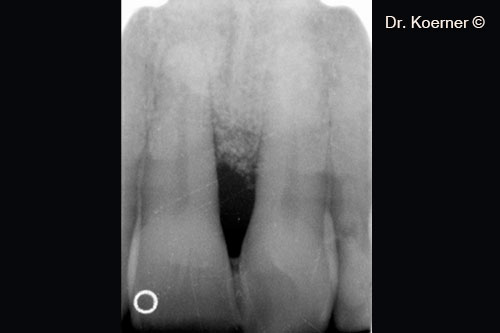

Chụp X-quang ban đầu